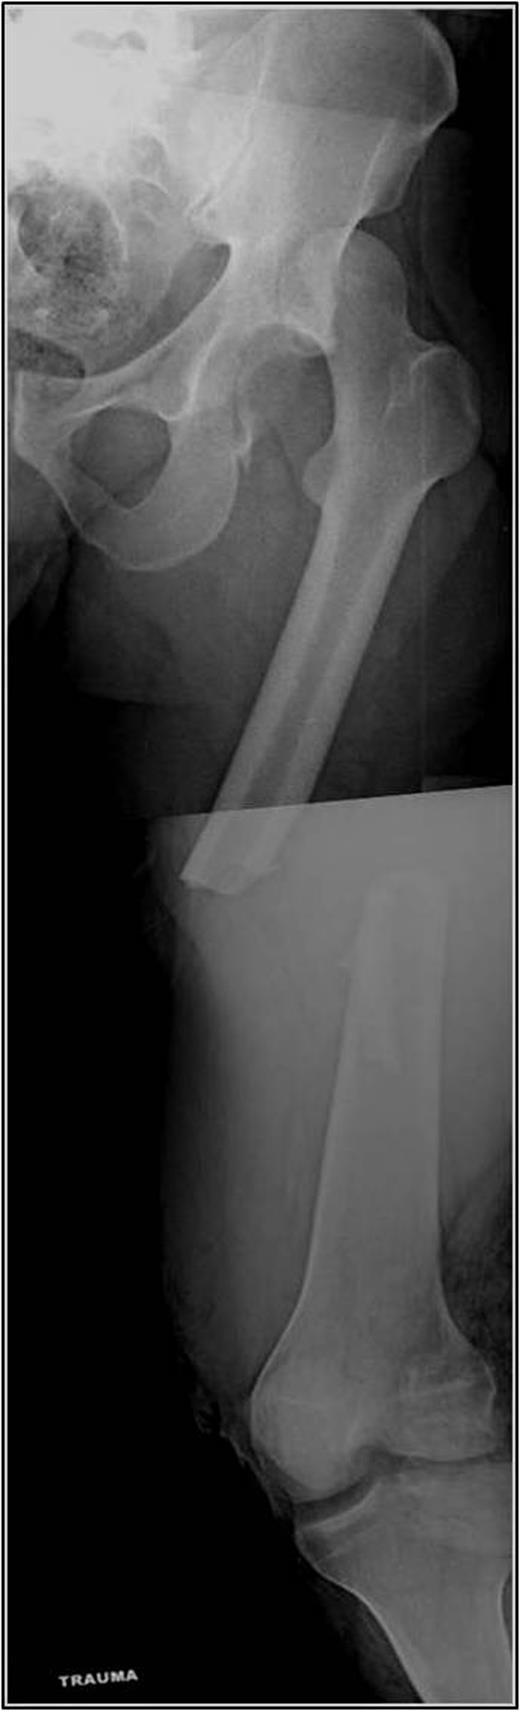

Operative management focused on closed reduction of the dislocated left hip. Two 5.0 mm Schanz pins with a carbon fiber bar (Zimmer, Warsaw, Indiana, USA) were placed in the proximal femur fragment. This was used to aid with the closed reduction maneuver of knee flexion, hip traction, adduction and internal rotation. Confirmed by intra-operative fluoroscopy, the femoral head was irreducible due to the engaging femoral head lesion on the acetabulum. A conversion to open reduction via a Kocher–Langenbeck approach in the lateral position ensued. The femoral head and posterior wall were reduced under direct visualization with two 3.5 mm pelvic reconstruction plates (Zimmer). The patient was moved to the supine position and underwent definitive femoral fixation with a retrograde, reamed femoral nail (Zimmer). Thigh compartments at the conclusion of the femoral fixation were tense and non-compressible, requiring a thigh compartment fasciotomy. Negative pressure therapy was placed over the incision and the knee laceration was primarily closed. After multiple washouts of his lateral fasciotomy incision, he was primarily closed 1 week after initial presentation. He was discharged non-weight bearing on his left lower extremity on post-operative day 22. Eleven months post-injury, he remains full weight bearing without assistance. He reports intermittent pain with ambulation and radiographs show early arthritic changes and heterotopic ossification of his left hip (Fig. 4).

AP pelvis 8 months status post-ORIF of posterior wall with retrograde femoral nail. The left hip demonstrates early post traumatic arthritis and heterotopic ossification.